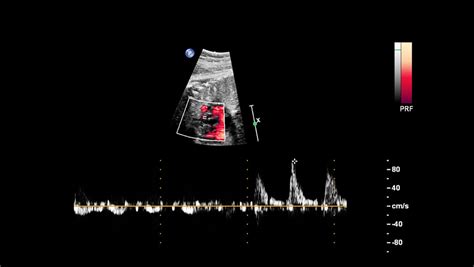

Biometria fetală este efectuată, în general, printr-o examinare cu ultrasunete. Undele ultrasonore sunt utilizate pentru a genera imagini ale fătului în uter, imagini ce sunt apoi analizate de către un specialist pentru a efectua măsurătorile necesare.

În timpul ecografiei, tehnicianul utilizează un traductor (un dispozitiv de mici dimensiuni) pentru a emite și a recepționa unde sonore. Aceste unde sonore se propagă prin corpul mamei și creează o imagine a fătului pe un ecran.

Progresul medicinei moderne a facilitat accesul la aparatură performantă, care permite surprinderea cu precizie îmbunătățită a unui număr tot mai mare de detalii. Ecografia obstetricală rămâne metoda principală utilizată pentru biometria fetală, fiind o tehnică neinvazivă, sigură și accesibilă.